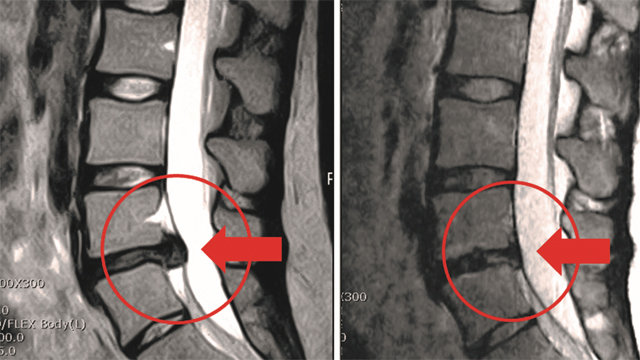

하이브리드 고주파 시술 전후 사진. 척추간 4-5번 추간판탈출증으로 허리부터 종아리까지 방사통을 호소했으나 시술 후 완쾌했다.